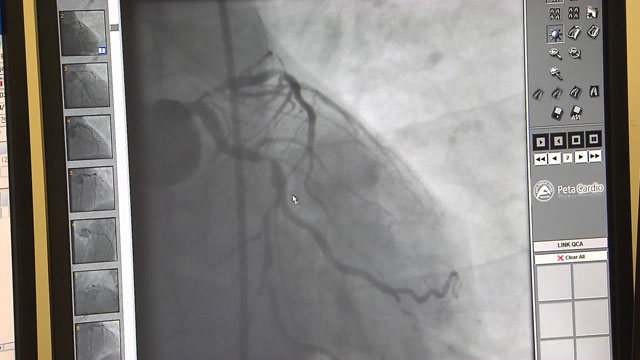

심근경색은 관상동맥 중 하나가 완전히 막혀서 심장 근육에 혈액 공급이 차단된 상태를 가리킵니다. 이로 인해 가슴 통증은 협심증보다 더 강하고 지속적이며, 호흡 곤란, 메스꺼움, 구역짐 등의 증상이 나타납니다. 심근경색은 생명에 직접적인 위험이 매우 높은 상황으로, 신속하고 적절한 응급 치료 없이는 생명에 심각한 영향을 미칠 수 있습니다.